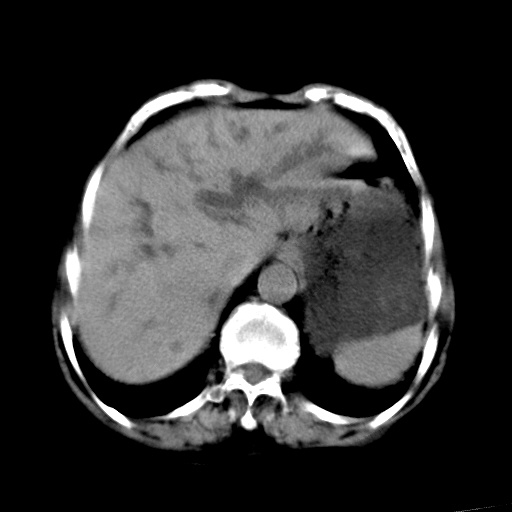

以下是引用杀毒软件在2009-3-4 17:38:00的发言:[br]为何没有喝照影剂呀? 胆总管及肝内胆管扩张,增强吧。[br][br]考虑-----十二指肠占位----建议----十二指肠镜检查[br][br]

以下是引用jiangjing在2009-3-4 17:45:00的发言:[br]低位胆道梗阻。十二指肠降段局部管壁增厚。扫描效果不理想,建议ct增强及ercp。

以下是引用杀毒软件在2009-3-4 17:38:00的发言:[br]为何没有喝照影剂呀? 胆总管及肝内胆管扩张,。增强吧。[br][br]考虑-----十二指肠占位----建议----十二指肠镜检查[br][br][br][br][本贴已被 杀毒软件 于 2009-3-4 17:56:38 修改过]